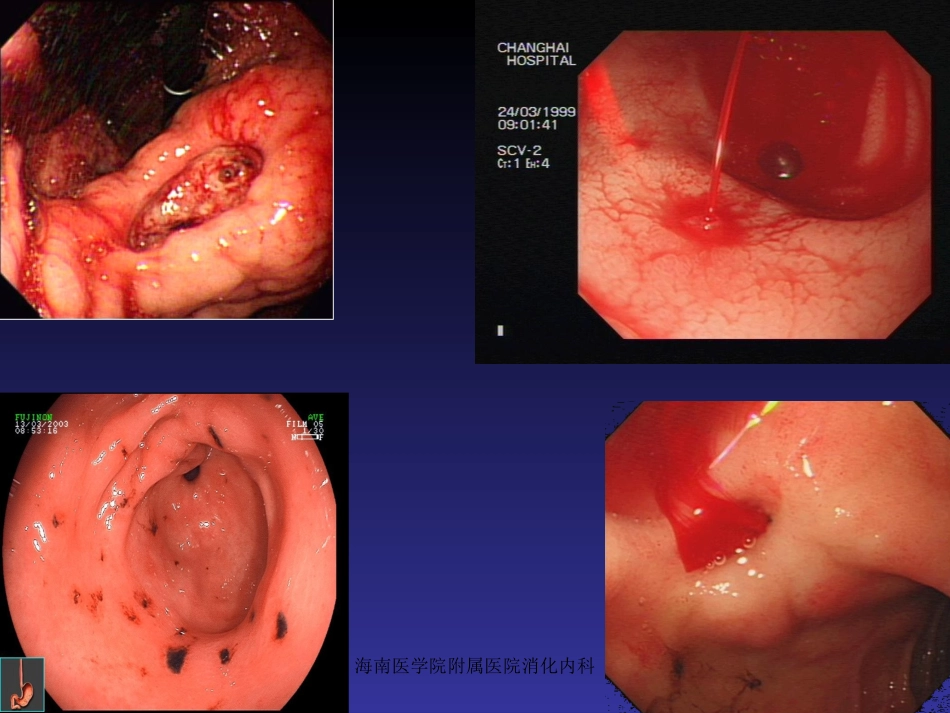

海南医学院附属医院消化内科•概述•胃、十二指肠出血分为:a)静脉曲张性出血b)非静脉曲张性出血消化性溃疡胃、十二指肠粘膜糜烂•非静脉曲肿瘤张性出血Dieculafoy氏溃疡血管畸形海南医学院附属医院消化内科海南医学院附属医院消化内科海南医学院附属医院消化内科海南医学院附属医院消化内科一.胃、十二指肠出血治疗方法•药物治疗•外科手术治疗•X线介入血管栓塞治疗•内镜下治疗内镜治疗优势:能够直观观察到胃、十二指肠出血部位,并能采取各种止血方法作相应止血治疗,从而避免以往常规外科手术治疗方法。海南医学院附属医院消化内科二、适应症与禁忌症适应症:•消化性溃疡并出血•Dieculafoy氏溃疡出血•急性胃粘膜病变并出血•血管畸形并出血•肿瘤并出血•Mallory-Weiss综合征•其他原因所致胃、十二指肠...